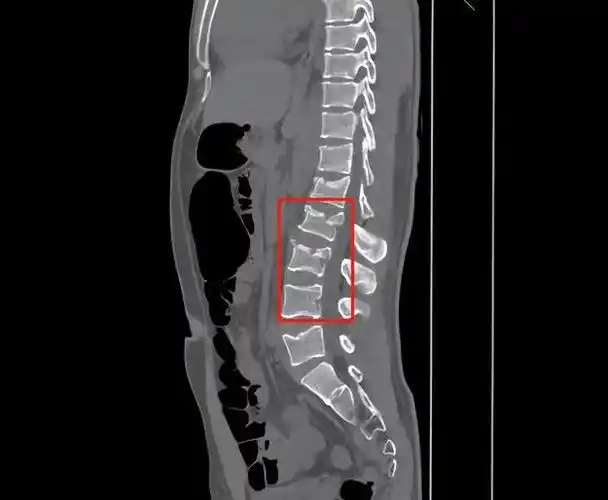

请教我读张腰椎ct片

ct检查后显示腰椎椎体1-3骨折.

这是一张腰椎ct片,我们能看到的问题节段,在l5-s1的b层到d层,椎体后缘